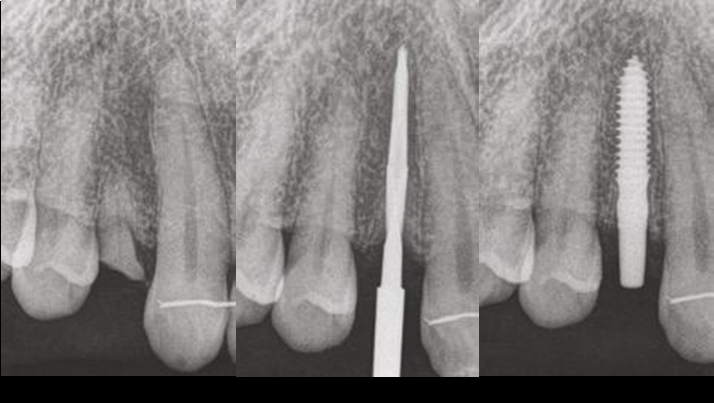

Clinical case: Patient-centered approach: treatment strategy for Root Membrane Technique & delayed implant placement

- Courtesy of Dr. Yoshiharu Hayashi, Japan -

Socket Shield Technique, anterior esthetics, maxillary anterior, esthetic, esthetics, delayed implant placement, socket preservation, AnyRidge, Root Membrane Kit, Root Membrane Technique, Partial Extraction Therapy, PET, esthetic zone, fuse abutment, Dr. Yoshiharu Hayashi,#11,#21,#22

AnyRidge implant system, fuse abutment Root membrane kit, PET Kit